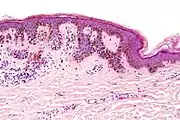

| Depth class | Location of nevus cells | Other characteristics | Image | ICD |

|---|---|---|---|---|

| Junctional nevus | Along the junction of the epidermis and the underlying dermis.[17] | May be colored and slightly raised.[18] | ![]() |

ICD10: D22 ICDO: M8740/0 |

| Compound nevus | Both the epidermis and dermis.[19] | ![]() |

ICD10: D22 (ILDS D22.L14) ICDO: 8760/0 | |

| Intradermal nevus | Within the dermis. | A classic mole or birthmark. It typically appears as an elevated, dome-shaped bump on the surface of the skin.[20] | ![]() |

Small dermal nevus, with nests of nevus cells (arrows)